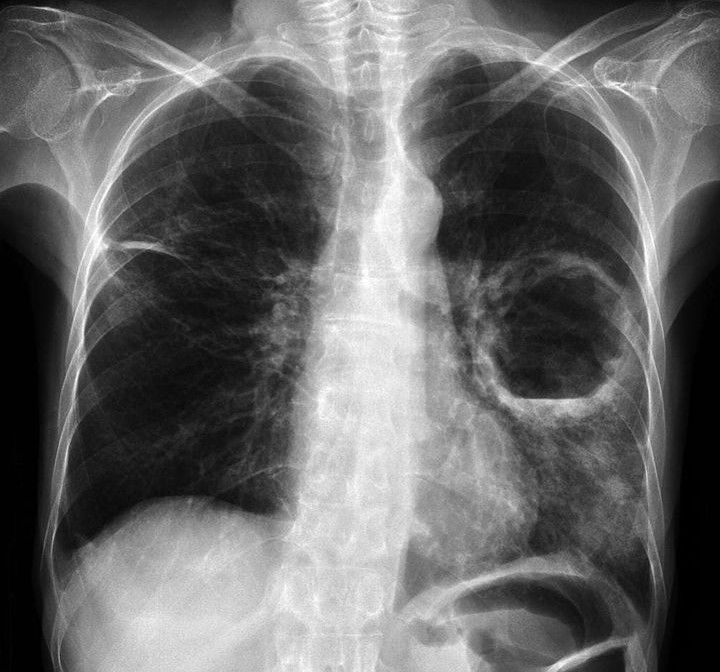

Identify the Pathology

Identify the pathology in the given radiograph.

Anish Chaudhuri

Scoliosis